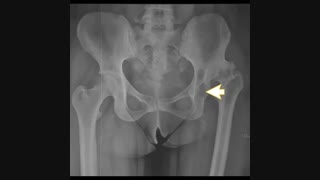

بسیاری از بیمارانی که نیاز به جراحی تعویض مفصل ران پیدا میکنند خانم هایی هستند که مفصل ران آنها به علت دررفتگی مادرزادی لگن خراب شده و دچار درد لگن و لنگش شده اند.

آیا همه دررفتگی های مادرزادی لگن نیاز به جراحی تعویض مفصل دارند. آیا کلا این دررفتکی ها باید عمل شوند. و آیا در صورت جراحی تا چه حد میتوان انتظار داشت تا درد و لنگش یا کوتاهی پای بیمار خوب شود